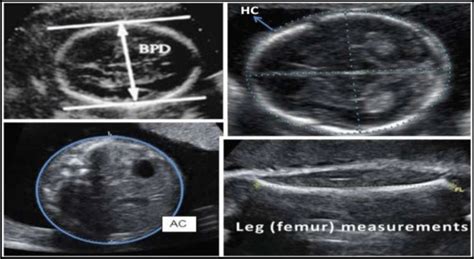

Decoding BPD: Biparietal Diameter

BPD, or Biparietal Diameter , measures the distance across your baby’s head from one parietal bone (side of the head) to the other. It’s one of the most commonly used measurements to assess fetal growth and estimate gestational age. Essentially, it’s a peek at how wide your baby’s head is. At 30 weeks, the normal range for BPD typically falls between 7.5 cm to 8.9 cm (or 75 mm to 89 mm) . However, remember that these ranges are just guidelines, and there can be variations. Factors like genetics, the baby’s position, and even the sonographer’s technique can influence the measurement. It’s also important to remember that these are just averages. A slightly higher or lower BPD measurement at 30 weeks doesn’t necessarily mean there’s a problem. For example, if the BPD is larger than average, it could indicate a larger baby, or it could be due to the baby’s head shape. On the other hand, a smaller BPD could be related to a smaller baby or the baby’s head shape. Your doctor will consider all the measurements together and assess the overall growth pattern. Also, doctors will use this measurement to estimate the gestational age of the baby and predict the delivery date. It’s a key part of your ultrasound report, so it’s good to understand what it represents. So, if you see BPD on your report, now you know what that means. If the BPD measurement seems outside of the normal range, the doctor might perform additional tests to assess the baby’s development and check for any potential issues. But don’t worry, this doesn’t always signal any problems. The doctor will explain it all in detail.

Decoding HC: Head Circumference

Next up, we have HC, or Head Circumference . This measurement is exactly what it sounds like: the distance around your baby’s head. It gives doctors a comprehensive view of the baby’s head size and growth. At 30 weeks, the normal range for HC is usually between 27.5 cm to 32.5 cm (or 275 mm to 325 mm) . The HC measurement is also crucial for evaluating fetal development. The HC measurement helps to monitor the baby’s overall growth and well-being. The head circumference, in conjunction with other measurements, provides a comprehensive picture of the baby’s growth.

Decoding AC: Abdominal Circumference

Now, let’s talk about AC, or Abdominal Circumference . This measurement indicates the circumference of your baby’s abdomen. The AC provides insights into the growth of the baby’s abdomen, including the liver and stomach. At 30 weeks, the normal range for AC typically falls between 24.0 cm to 29.0 cm (or 240 mm to 290 mm) . It’s a key indicator of your baby’s abdominal development. It is a vital measurement for assessing the growth of the baby’s abdominal area. This measurement can reflect the growth of organs in the abdomen, like the liver. It’s also an important factor in estimating the baby’s weight, which helps to estimate the size of the baby. It also helps to assess how much fat the baby has.

Decoding FL: Femur Length

Finally, we have FL, or Femur Length . This measurement is the length of your baby’s femur, which is the long bone in the thigh. It provides information about the baby’s skeletal development. At 30 weeks, the normal range for FL is usually between 5.4 cm to 6.6 cm (or 54 mm to 66 mm) . The FL measurement is used to assess the baby’s skeletal development and overall growth. It also helps in estimating the baby’s size. FL is also used in conjunction with other measurements to assess the baby’s overall growth and well-being. The FL measurement can help to screen for any skeletal abnormalities. It helps to monitor the baby’s growth and development.